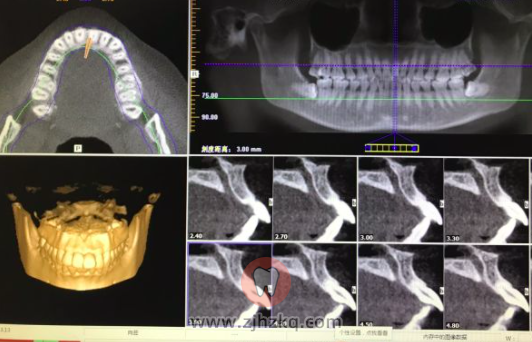

杭州博凡齿科拔智齿日记1205 杭城看牙记 • 2020年12月6日 11:34 • 看牙记 今天在杭州博凡齿科拔了左下阻生齿,仿佛过了一个世纪那么久,医生说只有15分钟 。 现在有点肿,疼痛感还好。 图片是杭口拍的,最终没有在杭口做 正在博凡西溪门诊卢院长给做矫正,上牙不走医保470一颗,下牙水平阻生1880一颗。 明天去拔下面的。 本文内容源自网络仅供参考,不作为诊断医疗依据,更多查询请 → 在线咨询客服